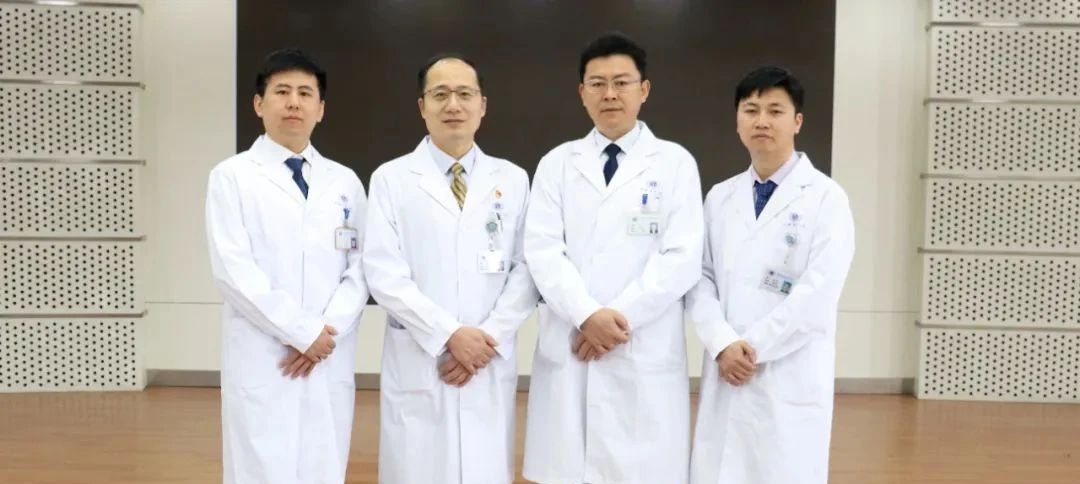

为减轻患者疼痛,改善髋关节功能,延缓股骨头坏死进展,在麻醉科、手术室团队的通力合作下,骨科张华,范志勇和关节亚专业团队张宏亮、张秉时、靳赢超为患者成功实施右股骨头坏死外科脱位+取髂骨植骨术。